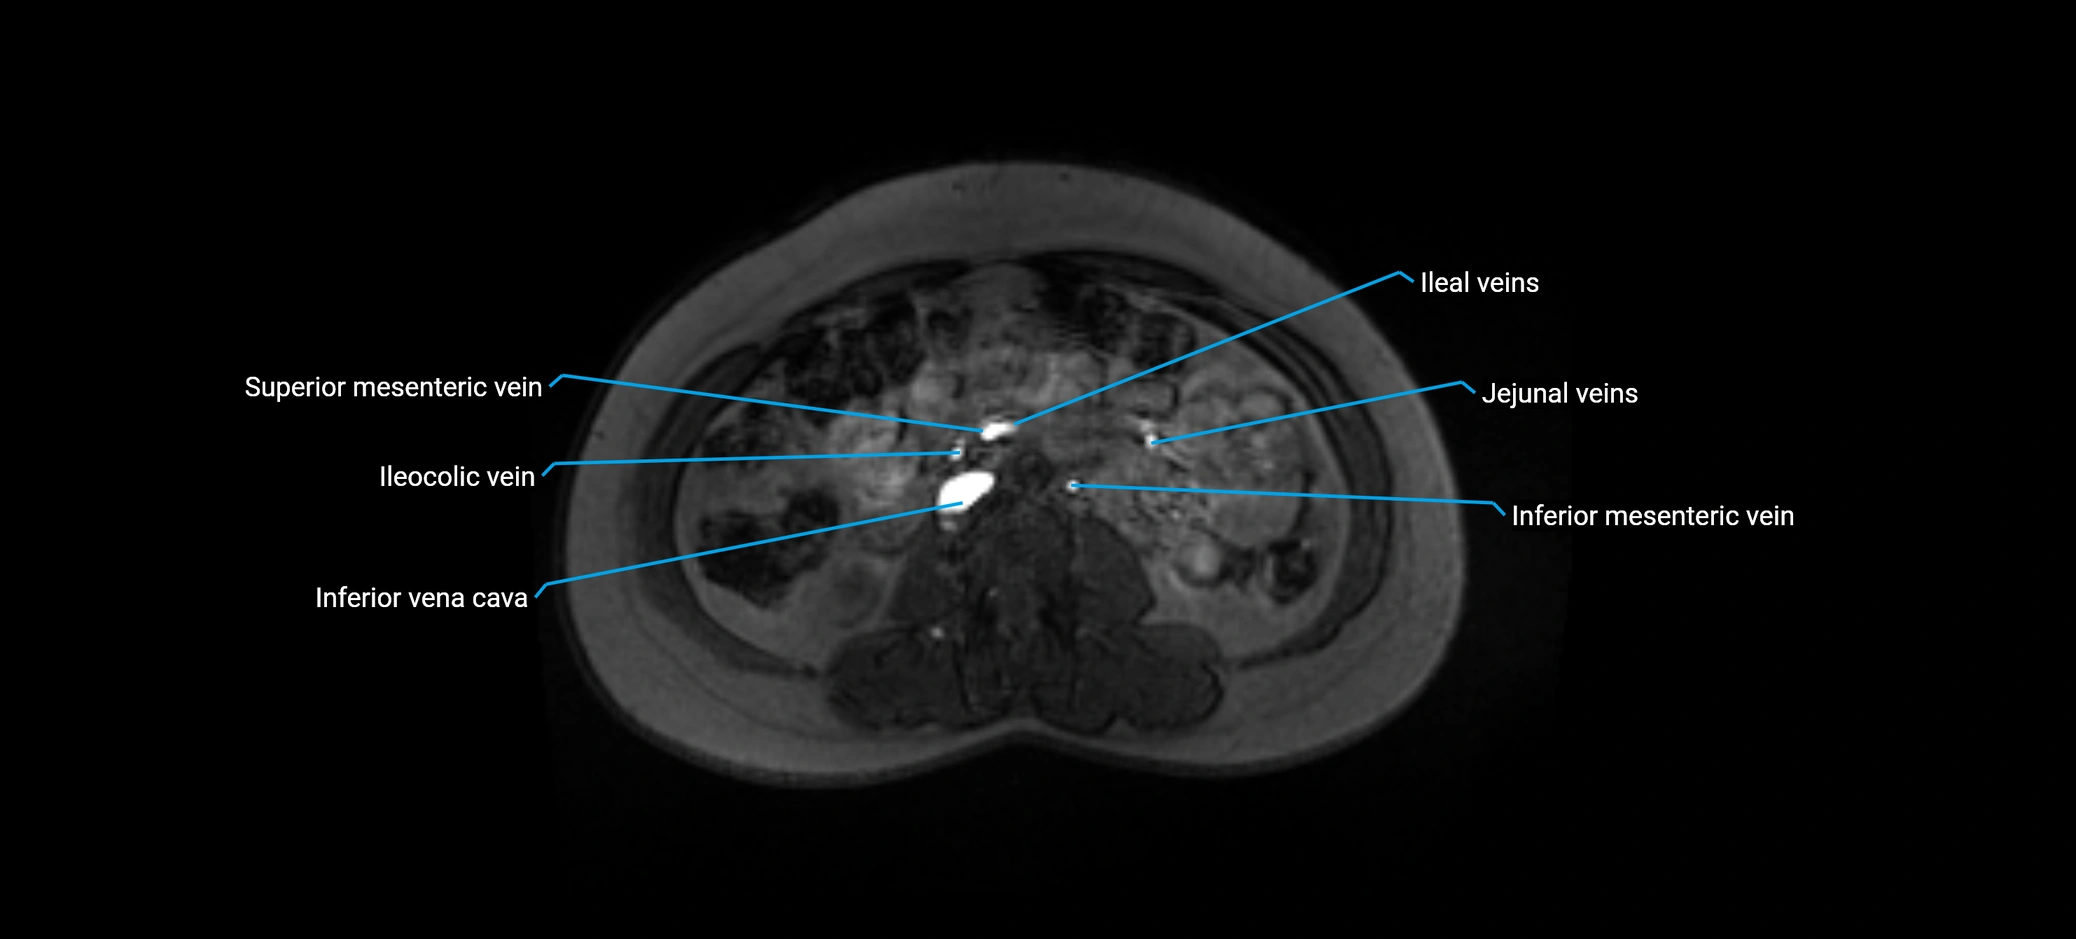

MRI image

image